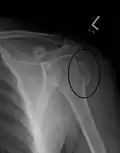

Humerus fracture

Proximal

Proximal humerus fractures most often occur among elderly people with osteoporosis who fall on an outstretched arm.[9] Less frequently, proximal fractures occur from motor vehicle accidents, gunshots, and violent muscle contractions from an electric shock or seizure.[10][5] Other risk factors for proximal fractures include having a low bone mineral density, having impaired vision and balance, and tobacco smoking.[11] A stress fracture of the proximal and shaft regions can occur after an excessive amount of throwing, such as pitching in baseball.[6]

Definitive diagnosis of humerus fractures is typically made through radiographic imaging. For proximal fractures, X-rays can be taken from a scapular anteroposterior (AP) view, which takes an image of the front of the shoulder region from an angle, a scapular Y view, which takes an image of the back of the shoulder region from an angle, and an axillar lateral view, which has the patient lie on his or her back, lift the bottom half of the arm up to the side, and have an image taken of the axilla region underneath the shoulder.[9] Fractures of the humerus shaft are usually correctly identified with radiographic images taken from the AP and lateral viewpoints.[12] Damage to the radial nerve from a shaft fracture can be identified by an inability to bend the hand backwards or by decreased sensation in the back of the hand.[5] Images of the distal region are often of poor quality due to the patient being unable to extend the elbow because of pain. If a severe distal fracture is suspected, then a computed tomography (CT) scan can provide greater detail of the fracture. Nondisplaced distal fractures may not be directly visible; they may only be visible due to fat being displaced because of internal bleeding in the elbow.[7]